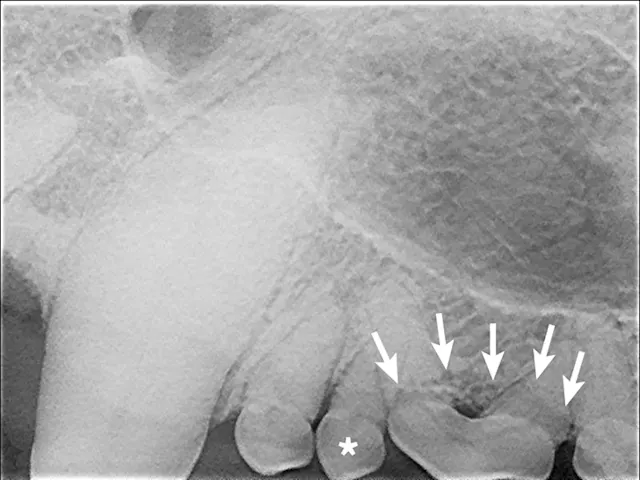

Full-mouth radiographs were obtained, with particular attention on the clinically missing mandibular premolars and the areas affected by gingival masses. Radiographs revealed unerupted mandibular 1st premolars situated in apparent cystic lesions, expansion of which resulted in involvement of the mandibular canines and 2nd premolar teeth. The apical portion of the mesial root of the mandibular premolar (306) was partially resorbed. Maxillary premolars were rotated bilaterally, but there were no periodontal consequences. Incidental findings included a supernumerary maxillary left first premolar 1 (205) and fusion of the roots of the left and right mandibular premolar 2 teeth (306 and 406). Horizontal alveolar bone loss was present at the area of 206, with radiolucency of the furcation area of 206 (Figures 3-6); the buccal aspect of 206 was covered by the gingival mass. Probing of the furcation was possible only from the palatal side and did not reveal furcation involvement.